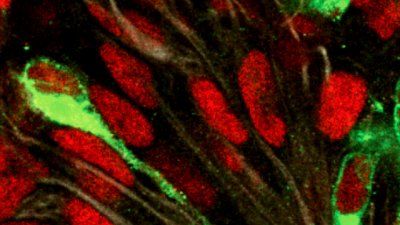

UCSF demonstrates that cancer is a clever engineer, capable of constructing entirely new disease-promoting networks out of raw materials readily available in the cell.